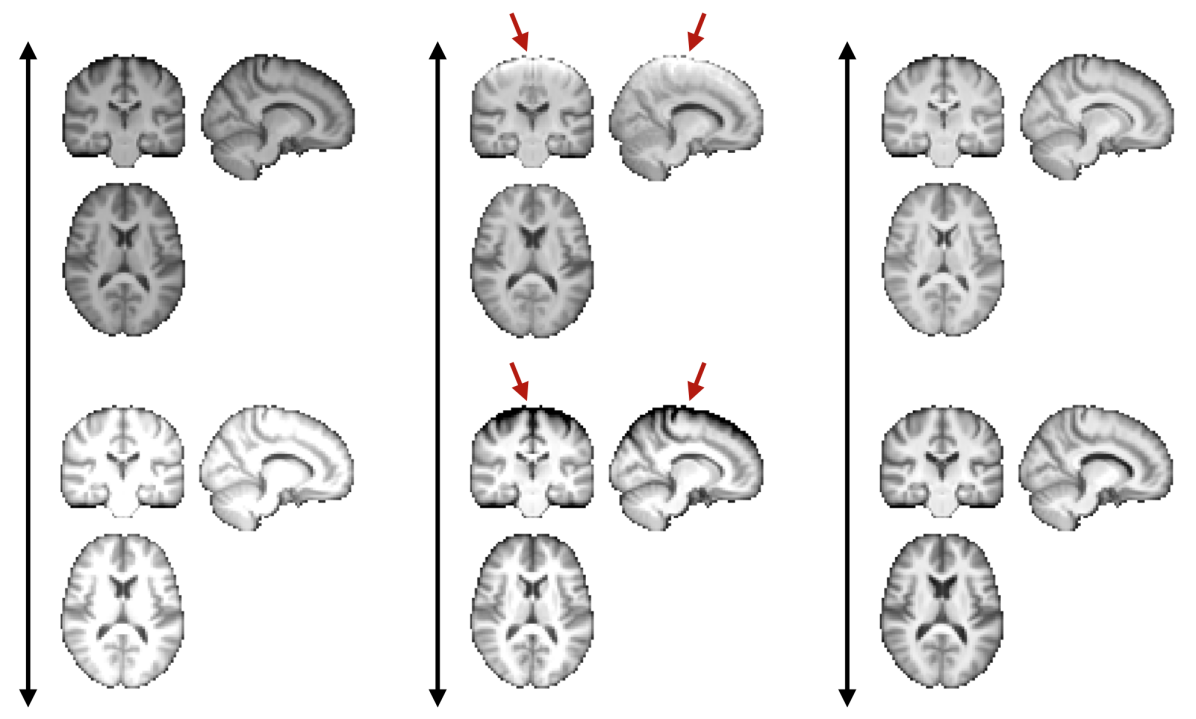

Proposed method: We performed all the experiments with the proposed method in Matlab, running on a Linux CPU machine (Intel Xeon E5-2660V3 10 Core CPU 2.60GHz, 128GB RAM). To speed up computations, the number of voxels was reduced by masking out the background (by thresholding the average of all images in each training set), and by downsampling the input data to a 3mm isotropic resolution. This downsampling was found not to affect the prediction performance in pilot experiments. For each training run, performance on the validation set was used to set the number of latent variables , which is the only hyperparameter of the method. An example of a model trained this way is shown in Figs. 3, 4 and 5.

| mode of variation | mode of variation | mode of variation |

A key advantage of the proposed method over discriminative methods such as RVoxM and SFCN is that, in addition to the discriminative map that it uses to make predictions, it also computes a generative map that expresses the causal effect of the variable of interest on brain morphology. To illustrate why this is important, Fig. 9 shows, for three different training set sizes, the discriminative map computed by our method for predicting age, along with the corresponding discriminative map of RVoXM and the SmoothGrad saliency map (Smilkov et al., 2017) – a generalization of linear spatial maps to nonlinear methods (Adebayo et al., 2018) – of SFCN. The inconsistencies of these maps across both the training set sizes and the different methods, and their overall lack of correspondence with the known neurobiology of aging, illustrate the difficulty of using discriminative maps for human interpretation.

More insight can be gained by examining the proposed method specifically, since it uses disciminative maps that are derived from generative ones. It is worth noting that estimating the generative maps from training data is itself quite stable, since it merely amounts to fitting two basis functions to hundreds of measurements in each voxel (cf. (8)). Furthermore, as illustrated in Fig. 10, the resulting maps are intuitive to interpret, since they show typical age-related effects such as cortical thinning and ventricle enlargement (Fjell et al., 2009; Fjell and Walhovd, 2010). When the discriminative maps are subsequently computed as , however, a strong dependency on the training set size is introduced, because the method explicitly controls the complexity of its noise model in response to the size of the available training set (the bias-variance trade-off of Sec. 4.4). can also capture peculiarities in the data that may be relevant for improving prediction performance, but not for human interpretation. An example of this was shown in Fig. 5, where overall brightness variations and residual MR bias field artifacts were picked up by the noise model. Through , such noise patterns can find their way into , producing hard-to-interpret spatial maps that no longer reflect the expected age-related brain atrophy patterns. This is clearly illustrated in Fig. 4, where the discriminative map is contrasted with the corresponding generative map .